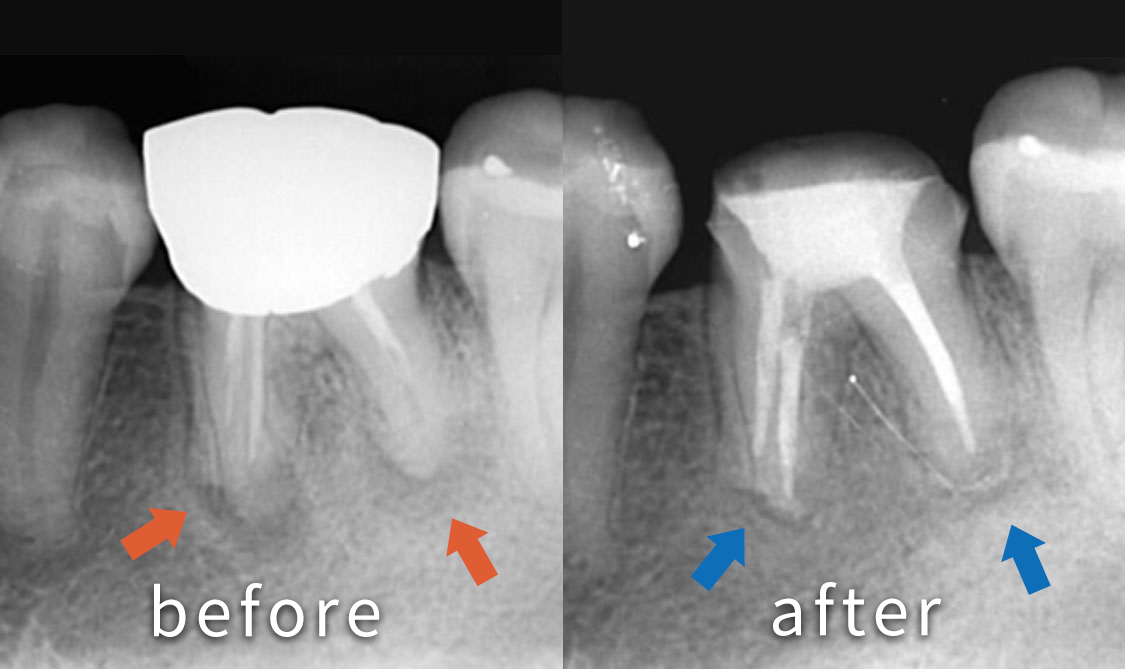

奥歯が痛くて噛めないといった悩みで来院された患者さんです。 レントゲンを撮影すると奥歯の根の先が膿んでいる状態でした。

根の中の古いお薬を取り除き、根の中を綺麗にした状態で新しいお薬を詰めています。根の先の病気(矢印の部分)の影が小さくなり、経過良好です。